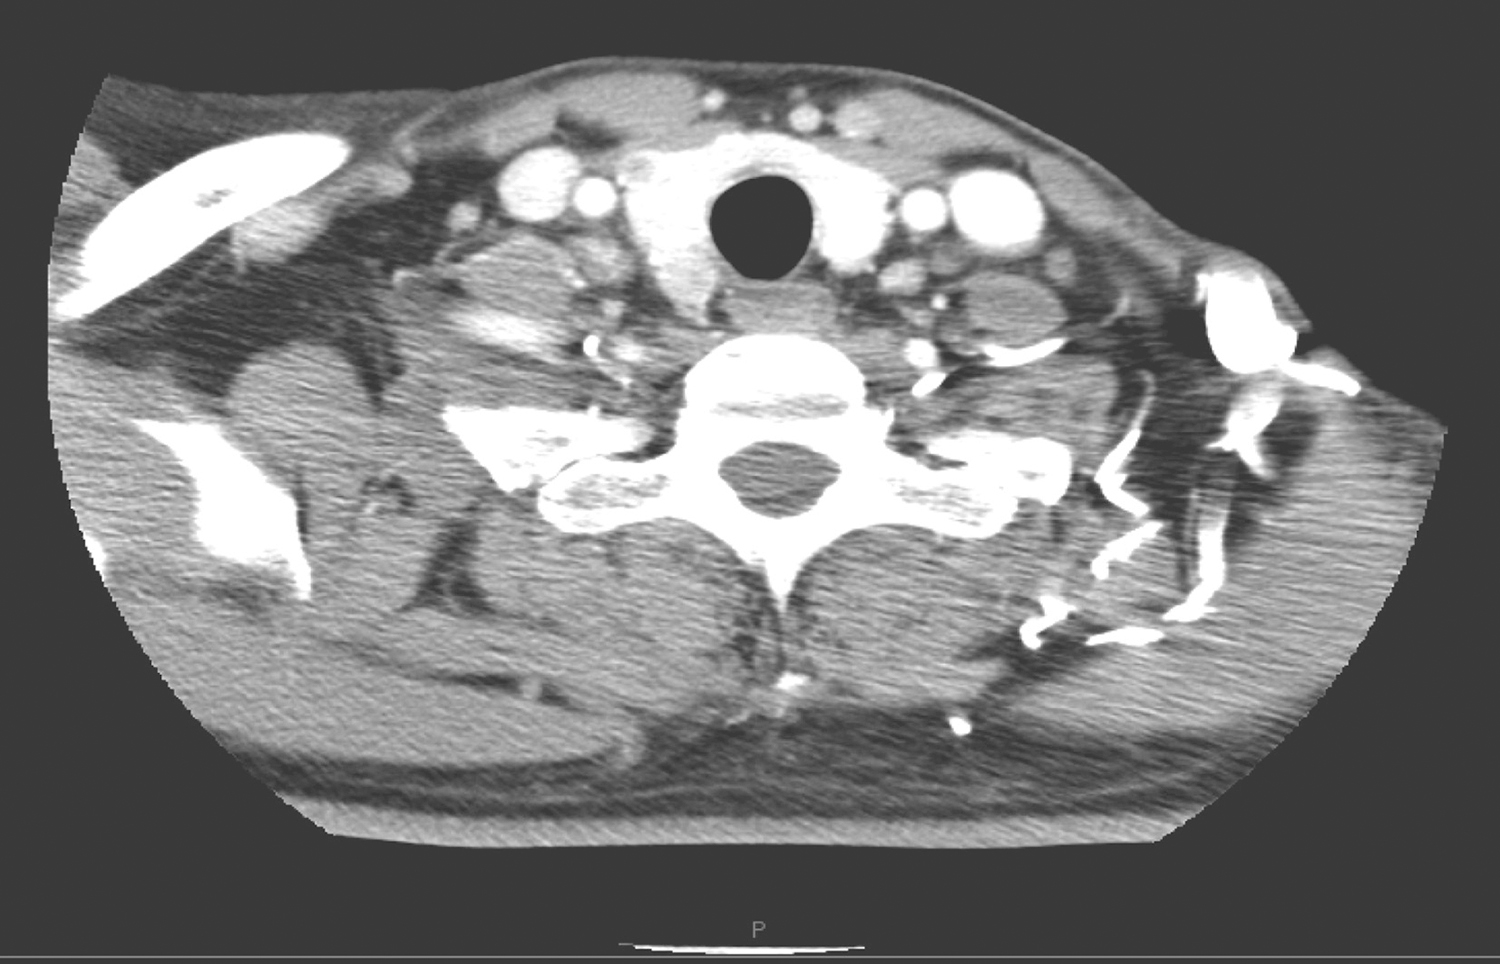

2.2013年10月10日,颈胸部CT检查所见:甲状腺左右叶内可见低密度结节,大者位于右叶,约1.6cm×1.2cm,其内可见高密度灶(图3)。扫描范围内鼻窦、鼻咽、口咽未见明确异常。

双颈深、右下颈甲状腺旁、双侧锁骨上、气管前、可见多发淋巴结肿大,部分明显强化,大者约1.2cm×0.9cm(图4~图6);余颈未见明显肿大淋巴结。

图3 颈部CT示甲状腺左右叶内低密度结节

图4 颈部增强CT示右颈肿大淋巴结

图5 颈部增强CT示双颈多发肿大淋巴结

图6 颈部增强CT示气管前及锁骨上肿大淋巴结